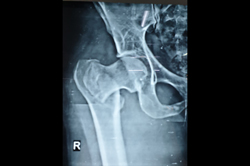

Neck Femur Fracture